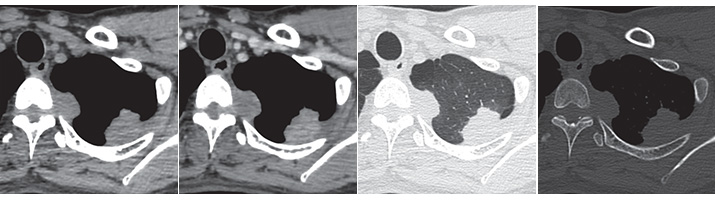

QUESTION NO.50